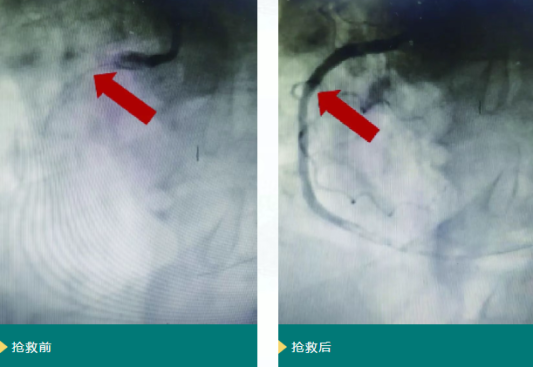

转入青岛西海岸第二医院后,心脏中心团队立即启动高危心梗救治流程,GRACE评分评估为高危(提示短期死亡风险高)。为避免心肌进一步坏死,团队决定紧急实施冠脉造影,结果显示患者右冠状动脉自中段完全闭塞。介入团队迅速操作,成功开通闭塞血管并植入1枚药物洗脱支架,手术全程顺利。目前患者生命体征平稳,已转入普通病房继续观察治疗。